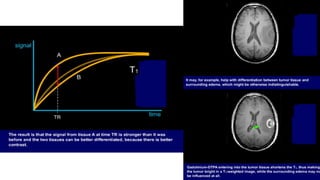

T1 WEIGHTED IMAGE

• Here, the magnitude of the LM indirectly determines the strength of

MR signal.

• Tilting of stronger LM by 90 degree RF pulse greater magnitude

of TM stronger MR signal.

• Tissues with short T1 regain their maximum LM in short time

(after RF pulse is switched off) when next RF pulse is sent

TM will be stronger resultant signal will be stronger.

• Therefore, material with short T1 have BRIGHT signal on T1 weighted

image.

HOW does one make images T1 weighted?

This is done by keeping the TR SHORT.

T2 WEIGHTED IMAGE

• Immediately after its formation TM has greatest magnitude and

produces strong signal . When it starts decreasing gradually

reduction of the intensity of received signal.

• Different tissues ,depending on their T2 ,have variable time for which

TM will remain strong enough to induce signal.

• Tissues with longer T2 , such as water ,will retain signal for longer

time and tissues with shorter T2 , will lose their signal earlier after RF

pulse is turned off.

How does one make images T2 weighted?

This is done by keeping the TE longer.